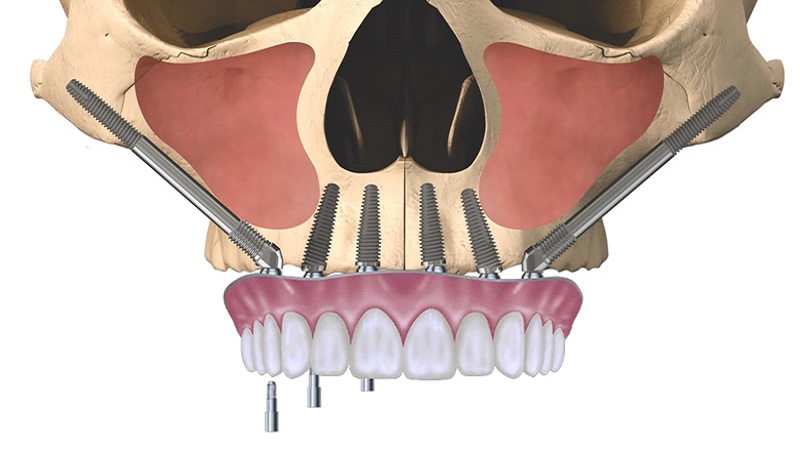

- ایمپلنت دندان اصفهان

- پروتز های دندانی در اصفهان